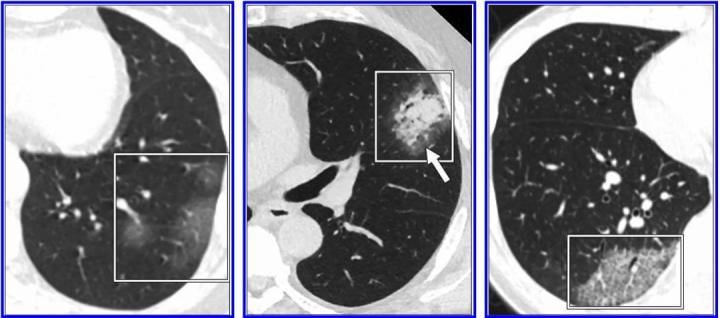

According to the 10 authors from multiple institutions across the US who reviewed the most frequently cited studies on the subject: 'Test performance and management issues arise when inappropriate and potentially overreaching conclusions regarding the diagnostic performance of CT for COVID-19 pneumonia are based on low-quality studies with biased cohorts, confounding variables, and faulty design characteristics. Image courtesy of American Journal of Roentgenology (AJR)

The specificity and positive predictive value of a laboratory test — in the case of COVID-19, reverse transcription-polymerase chain reaction (RT-PCR) — are based on its ability to limit false-positive findings. Acknowledging false-positive RT-PCR results are possible, Raptis, Henry, et al. maintained they are often caused by contamination and are likely insignificant in the setting of assays for COVID-19. CT, on the other hand, does not test for singular features unique to the disease, and even those features most characteristic of COVID-19 pneumonia — peripheral, bilateral ground-glass opacities typically in the lower lobes — have been reported in a number of other conditions, both infectious and noninfectious.

"At present," the authors of this AJR article concluded, "CT should be reserved for evaluation of complications of COVID-19 pneumonia or for assessment if alternative diagnoses are suspected."